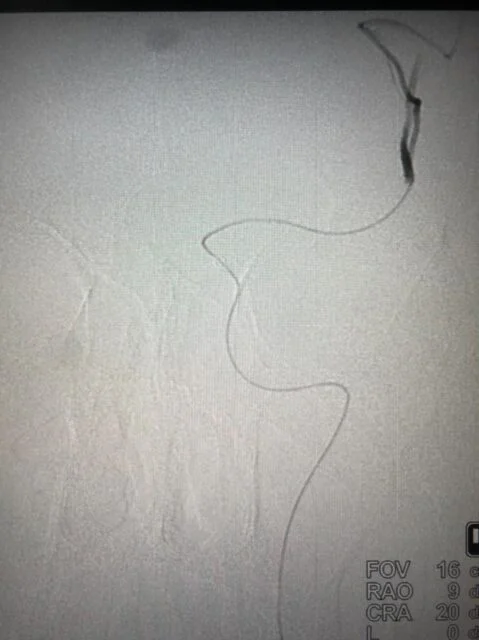

Successful Mechanical Thrombectomy in a relatively young stroke patient at ACCORD SUPERSPECIALITY HOSPITAL - A new hope for a large vessel stroke.